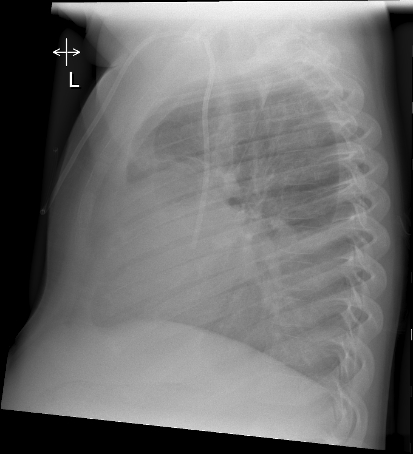

A chest X-ray with posterioanterior, lateral and left lateral decubitus views was also obtained: